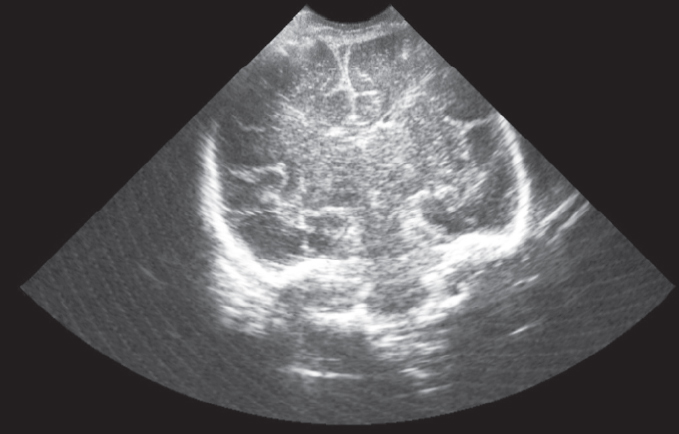

Родился живой ребенок (девочка) с МТ 1840 г, длиной 38 см, с оценкой по шкале Апгар 5/6 баллов. С рождения состояние ребенка расценивалось как тяжелое за счет дыхательной недостаточности (течение респираторного дистресс-синдрома), в связи с чем был переведен на аппаратную вентиляцию легких. За время лечения в отделении реанимации новорожденных ПЦ состояние ребенка улучшилось — на 8-е сутки выполнены экстубация и перевод на NCPAP, а с 10-х суток респираторная поддержка отменена. В неврологическом статусе очаговой и общемозговой симптоматики не выявлено. При проведении скрининговой краниальной сонограммы структурных нарушений не выявлено, церебральная зрелость по нейровизуализационным критериям соответствовала гестационному возрасту ребенка (рис. 5).

Рис. 5. Краниальная сонограмма новорожденного ребенка в 34 нед. гестации. Фронтальный скан (норма). Визуализируются вторичные извилины коры больших полушарий

Количественные характеристики церебрального кровотока свидетельствовали об удовлетворительной церебральной перфузии (рис. 6).

Рис. 6. Исследование кровотока в передней мозговой артерии новорожденного ребенка. Количественные характеристики допплеровского спектра кровотока в пределах нормы, нормальное периферическое сопротивление